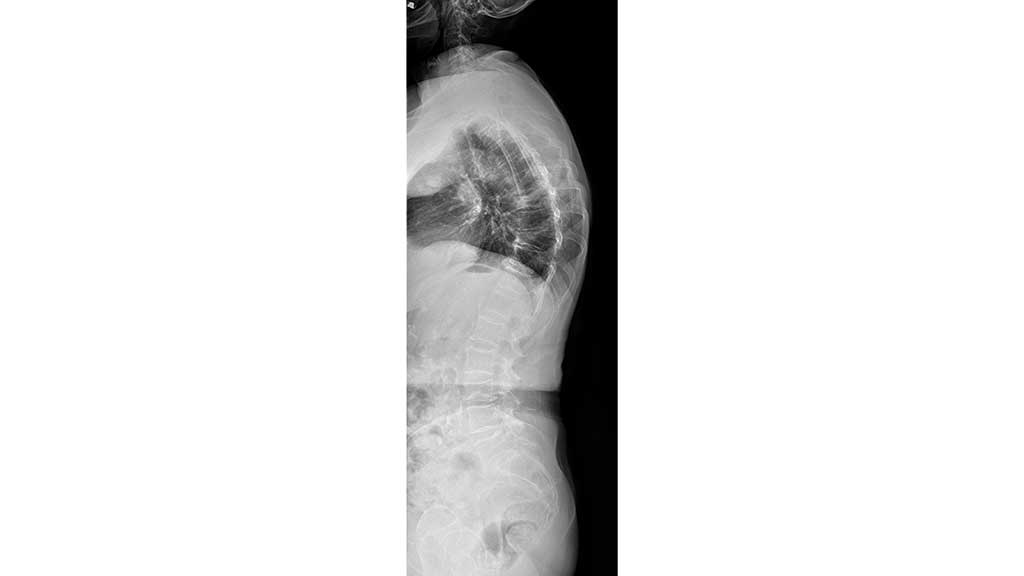

Osteoporose stellt in unserer alternden Gesellschaft eine stetig wachsende Herausforderung dar. Die Verminderung des Mineralgehaltes der Knochen führt zur Änderung der Spongiosa-Architektur und zur Reduktion der Knochenmasse, was Mikrofrakturen, Spontanfrakturen, Frakturen durch Bagatelltraumata sowie nachfolgende Fehlstellungen nach sich ziehen kann (Abb. 1).